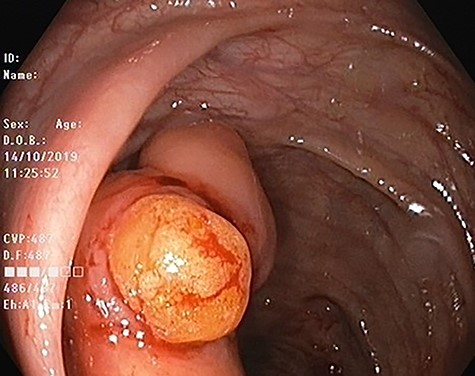

Our patient is 56-year-old female, a known case of locally advanced breast carcinoma. She was initially managed by chemotherapy followed by modified radical mastectomy then adjuvant radiotherapy and chemotherapy. The patient gave a positive family history of colon cancer; therefore, genetic testing for adenomatous polyposis coli (APC) mutation and surveillance colonoscopy were recommended by genetic counselor. The APC gene mutation came to be positive and as part of the work up for her primary disease, computed tomography (CT) scan of the abdomen performed and showed evidence of 4 cm intraluminal lesion in the ascending colon suggestive of lipoma without bowel obstruction (Fig. 1). As a result of these findings, colonoscopy was performed and it revealed a large smooth intraluminal subepithelial lesion in the ascending colon occupying one third of the lumen circumference (Fig. 2). With the use of biopsy forceps, indentation of the tumor can be seen, which is as known as “pillow sign” and once a biopsy taken, a fatty yellowish material was seen protruding from the biopsy site suggestive of lipoma (Fig. 3). Histopathological examination showed multiple fragment of normal colonic mucosa and fragments of mature adipose tissue consistent with lipoma (Fig. 4, black arrows). Clinically, the patient denied history of abdominal pain, rectal bleeding, changes in her bowel habit and intestinal obstruction symptoms. She denied any personal history of malignancy or lipoma. On physical examination, there was no evidence of any lipomas in particular her scalp, limbs or trunk. Although she has no gastrointestinal symptoms attributed to the lipoma, given that it is large in size and she is in clinical and radiological remission, we referred her for the opinion of colorectal surgery.

Colonoscopic image of ascending colon lipoma showing normal mucosa.